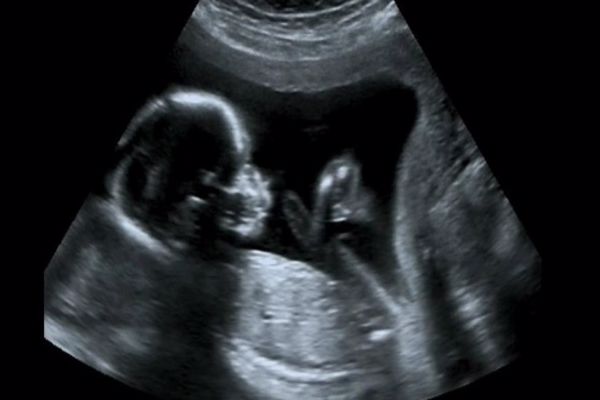

2- وفي حال حدوث زواج بين الأقارب، يجب استشارة الأطباء وإجراء الفحوص الطبية اللازمة، قبل اتخاذ قرار الزواج، وقبل الحمل، وخلال فترة الحمل، لتجنّب إصابة الجنين بالتشوهات.